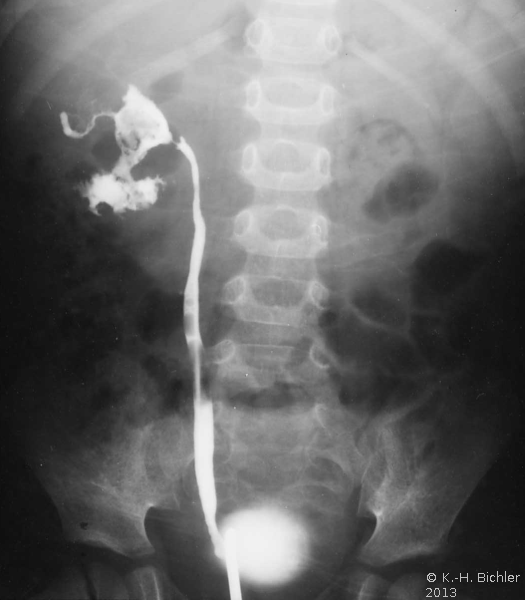

Sie tritt zumeist bei Patienten mit Diabetes Mellitus bzw. bei Harnwegsobstruktionen auf (Komplizierte Pyelonephritis). Dabei können eine oder alle Papillen befallen sein. Histologisch findet sich eine koagolative Infarktnekrose, d.h. die Umrisse von befallenen Tubuli sind erhalten. Leukozytäre Reaktionen finden sich an den Rändern der Nekrosebezirke Literatur:Robbins: "Pathologic Basis of Disease", Saunders Philadelphia, 1999.